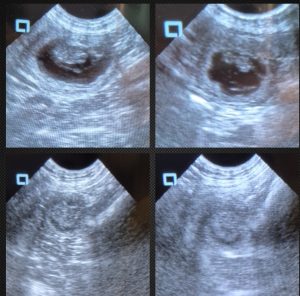

Recently, experienced breeder Joanne Smith shared a powerful example of how regular scanning at home can change outcomes. She was monitoring a singleton pregnancy with her ScanPad ultrasound machine when she discovered that the fetus was no longer viable.

Thanks to her previous scans, she was able to document the process of fetal resorption with before-and-after images—something rarely captured so clearly. This insight allowed her to continue monitoring the dam without unnecessary transport or stress, reinforcing how vital at-home canine pregnancy ultrasound can be.

Joanne’s images (above) clearly show the process of resorption.